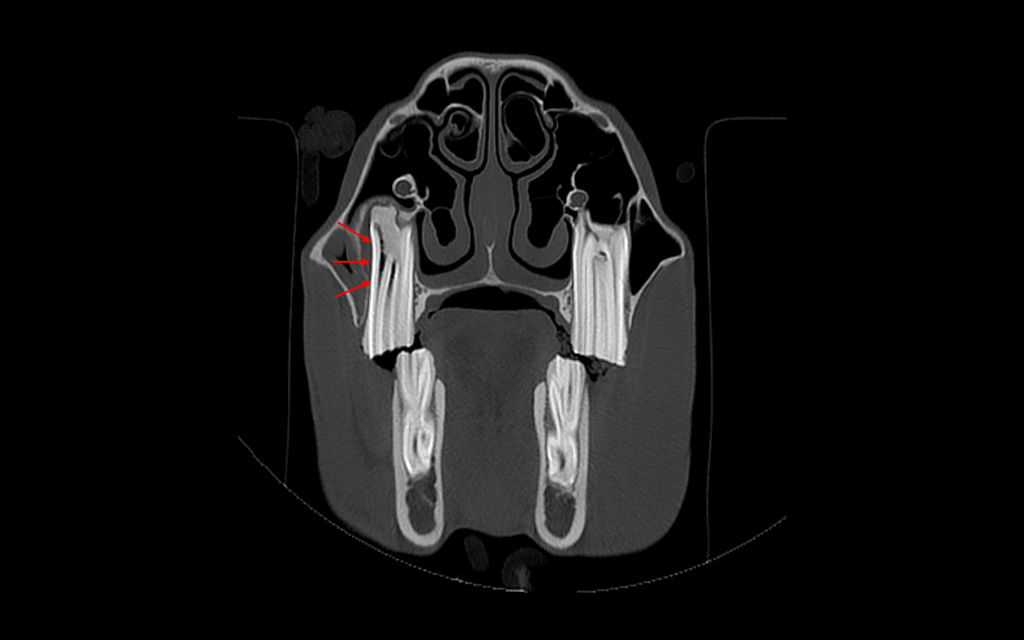

Bone window, transverse image, tooth 109, buccal wall discontinuity, gas inclusions, periodontal changes

Apical infection of tooth 109 with secondary sinusitis.

Radiographs showed abnormal pulp horns, an occlusal fissure, root shortening, and alveolar sclerosis, while CT revealed mucosal thickening in the maxillary sinuses, buccal wall discontinuity, and gas inclusions in the periodontal space and pulp chamber.